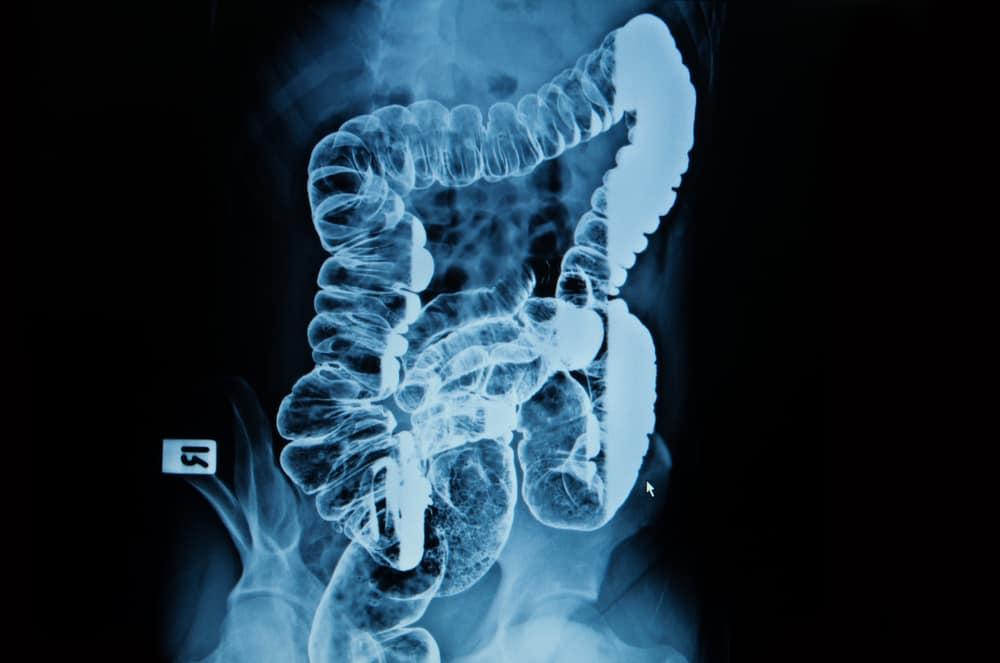

Barium enema adalah pemeriksaan sinar-X yang dilakukan pada saluran pencernaan bawah. Prosedur ini dilakukan untuk mendeteksi perubahan atau kelainan pada usus besar atau kolon. Barium enema dikenal juga dengan sebutan colon X-ray.

Prosedur barium enema melibatkan penuangan cairan barium sulfat ke dalam usus besar. Barium dapat menyerap sinar-X dan tampak berwarna putih dalam foto rontgen. Pola cairan akan menunjukkan apa penyebab masalah pada usus besar Anda.

Barium enema adalah pemeriksaan penunjang untuk mendeteksi kelainan pada usus besar. Prosedur ini dilakukan dengan memasukkan barium cair ke dalam usus besar sehingga kelainan dapat dideteksi melalui foto rontgen.